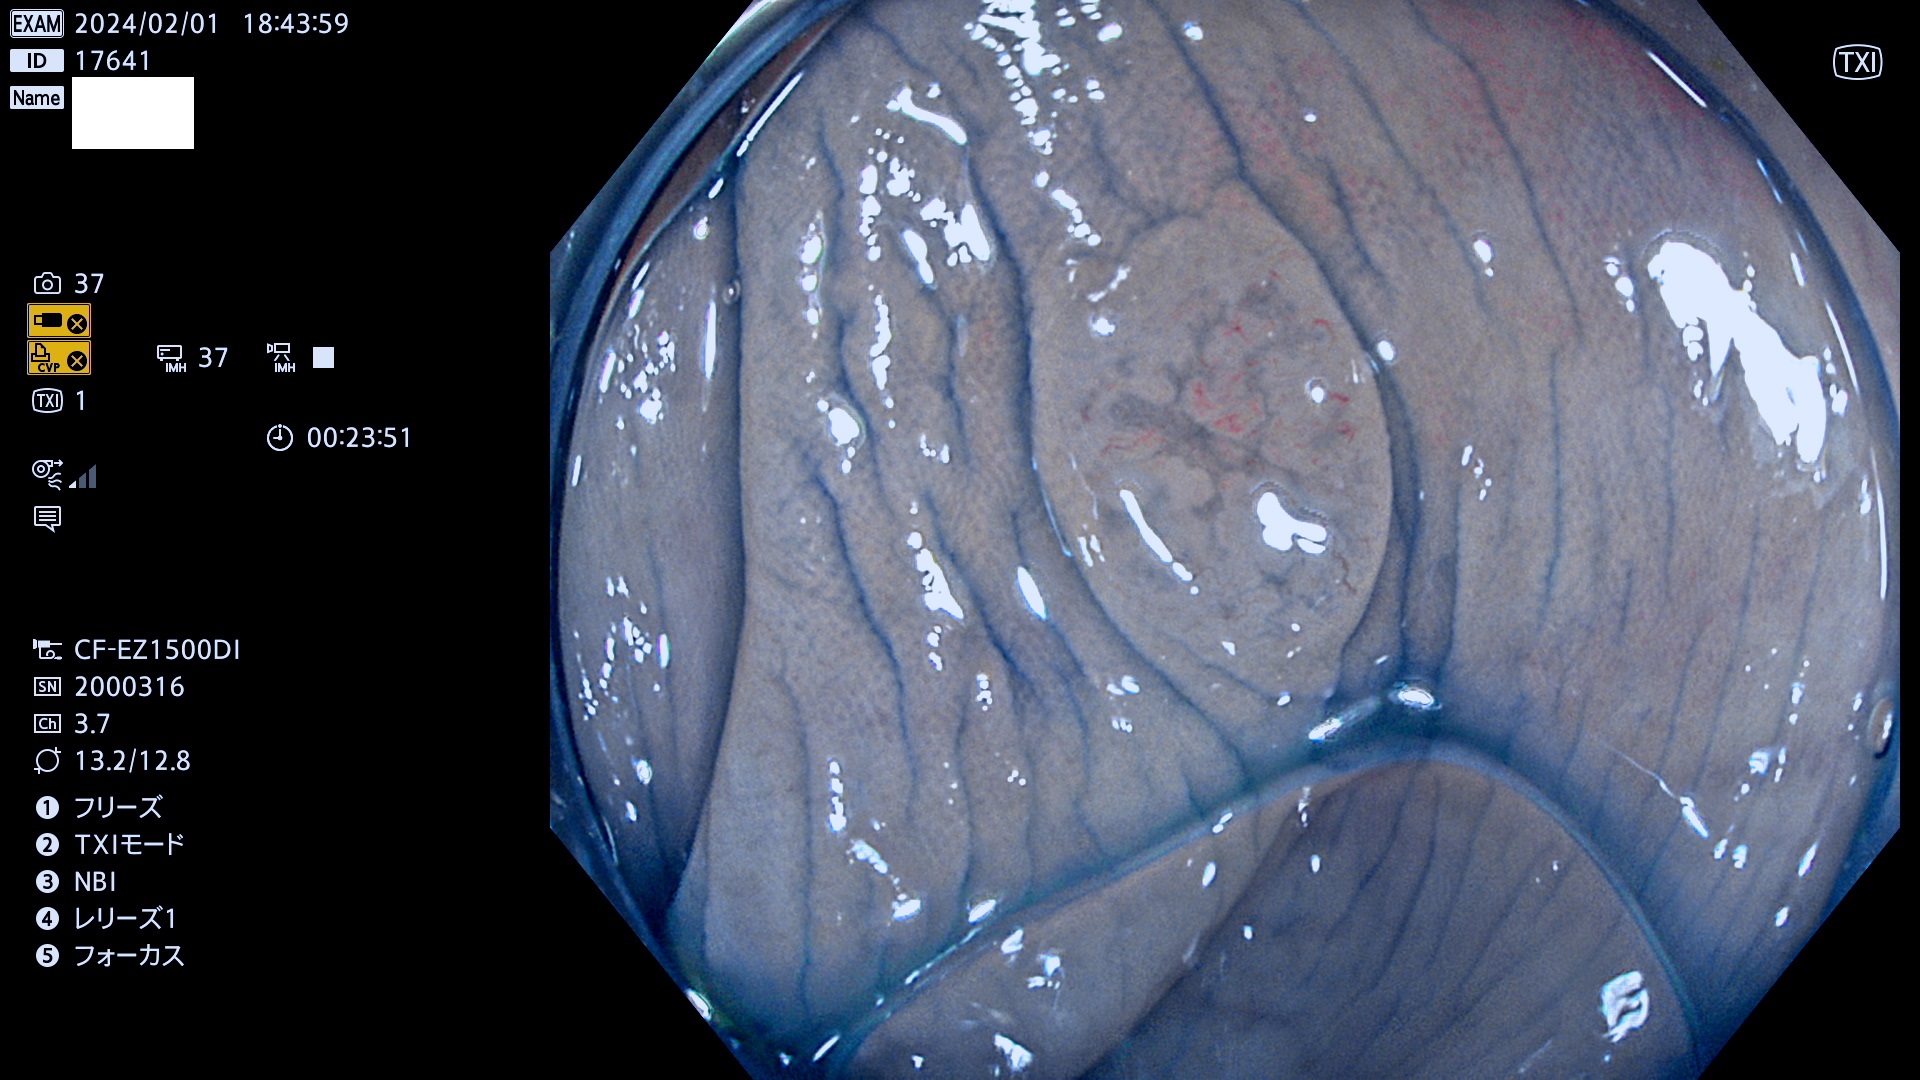

表面型腺腫(Flat Adenoma)の中で、完全に平坦な物をUb、陥凹している物をUcと呼びます。平坦隆起型(Ua)よりも、発見が難しく危険な病変です。

毎週の検査(木・金・土・日)に発見されたUb、Uc型・腺腫を、その週の日曜の夜にUPし1週間、提示します。

抽出の対象期間 2024年2月1日(木)〜2月4(日)の4日間(40件の検査)12件